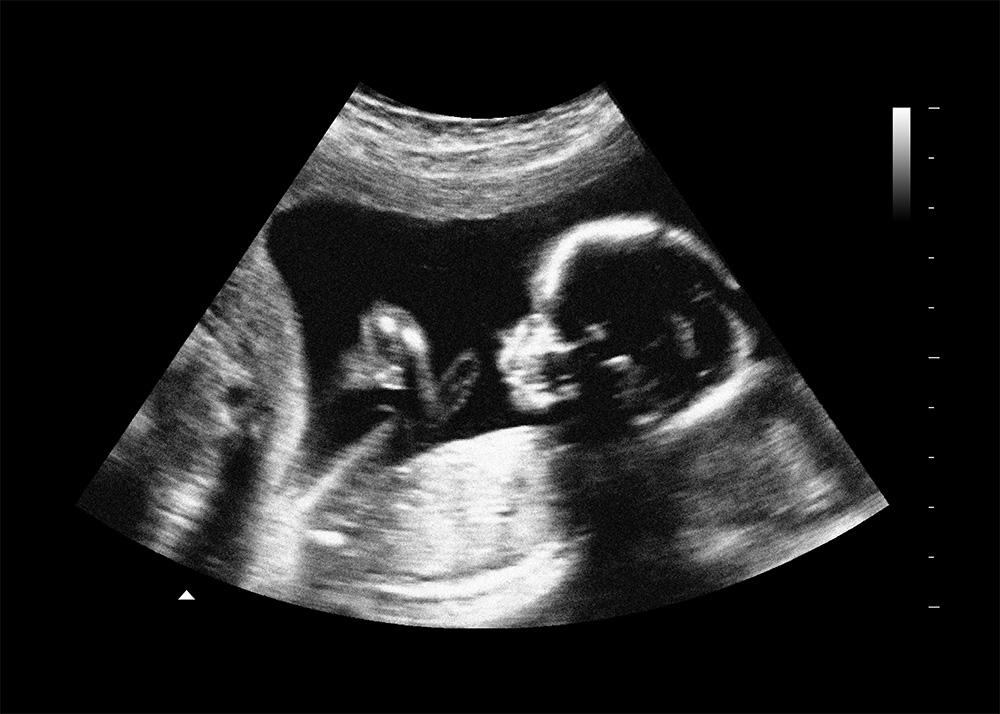

Late one night, Adreiona called a PreBorn! Pregnancy Clinic in a panic. “I took the abortion pill,” she said. “Everyone is telling me that since I am in college, I can’t manage a baby. Is it too late to save my baby?” she pleaded.

Sadly, the abortion industry sells a deceptive message that the abortion pill is an easy fix to a complicated situation. However, it is not that simple. Many girls take the abortion pill only to later regret their decision. Thankfully, there is a life-giving solution called the abortion pill reversal! If taken within 72 hours, the life of the baby can be saved.

Donors like you faithfully provide ultrasounds and counseling while helping to fund baby clothes, diapers, and formula. More importantly, your love gives a young mother an opportunity to hear the gospel of Jesus Christ. Check out the powerful impact our love makes.